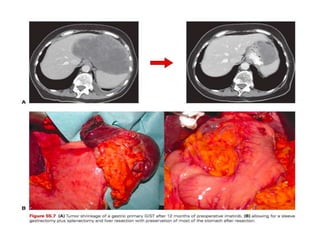

• Preoperative imatinib can shrink gastric, periampullary, or

rectal GISTs to such an extent as to allow more limited

excisions.